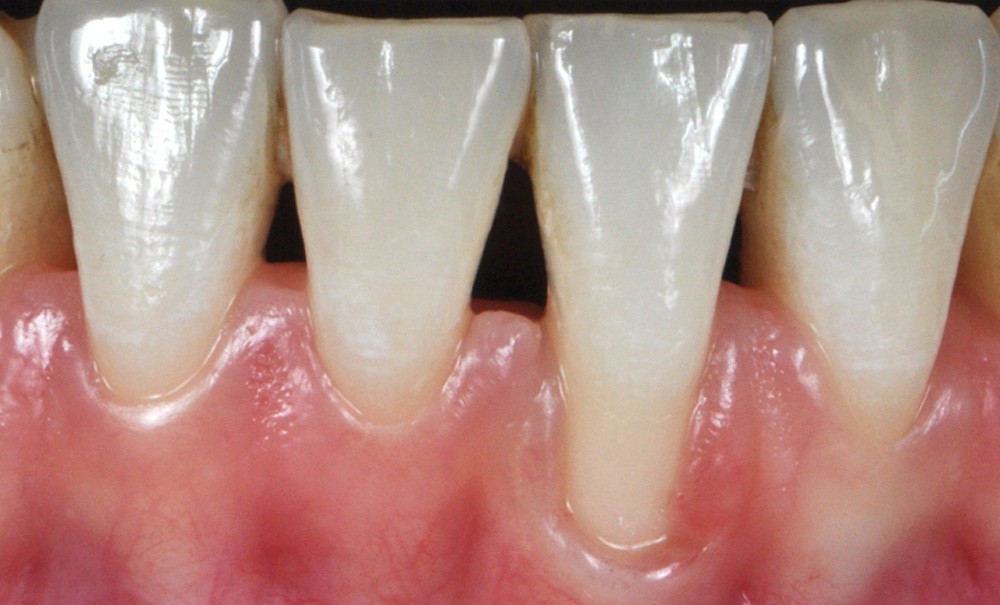

Les facteurs prédisposants combinés aux causes directes traumatiques ou inflammatoires contribuent à l’apparition de récession. Ces facteurs sont : le phénotype fin, la proéminence radiculaire (fig. 4), la malposition dentaire (fig. 5), le traitement orthodontique et les insertions de freins…